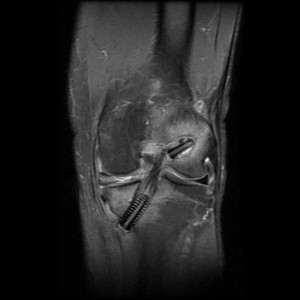

Bu dokular açık cerrahi ile alınır. Bunun için yaklaşık 3-4 cm lik küçük kesiler kullanılır. Daha sonra artroskopik olarak (gelişmiş merkezlerde) diz içindeki ACL artıkları temizlenir ve ACL nin orjinal yerlerine uyan tibia ve femur kemiklerine 2 tünel açılır. Bu tüneller içine alınan doku yerleştirilir ve uygun gerginlikte tünellere vida, tel çivi gibi maddelerle fikse edilir. Ameliyat sonrası genellikle dizlik uygulanır.

erdincmordumanaclintrafix